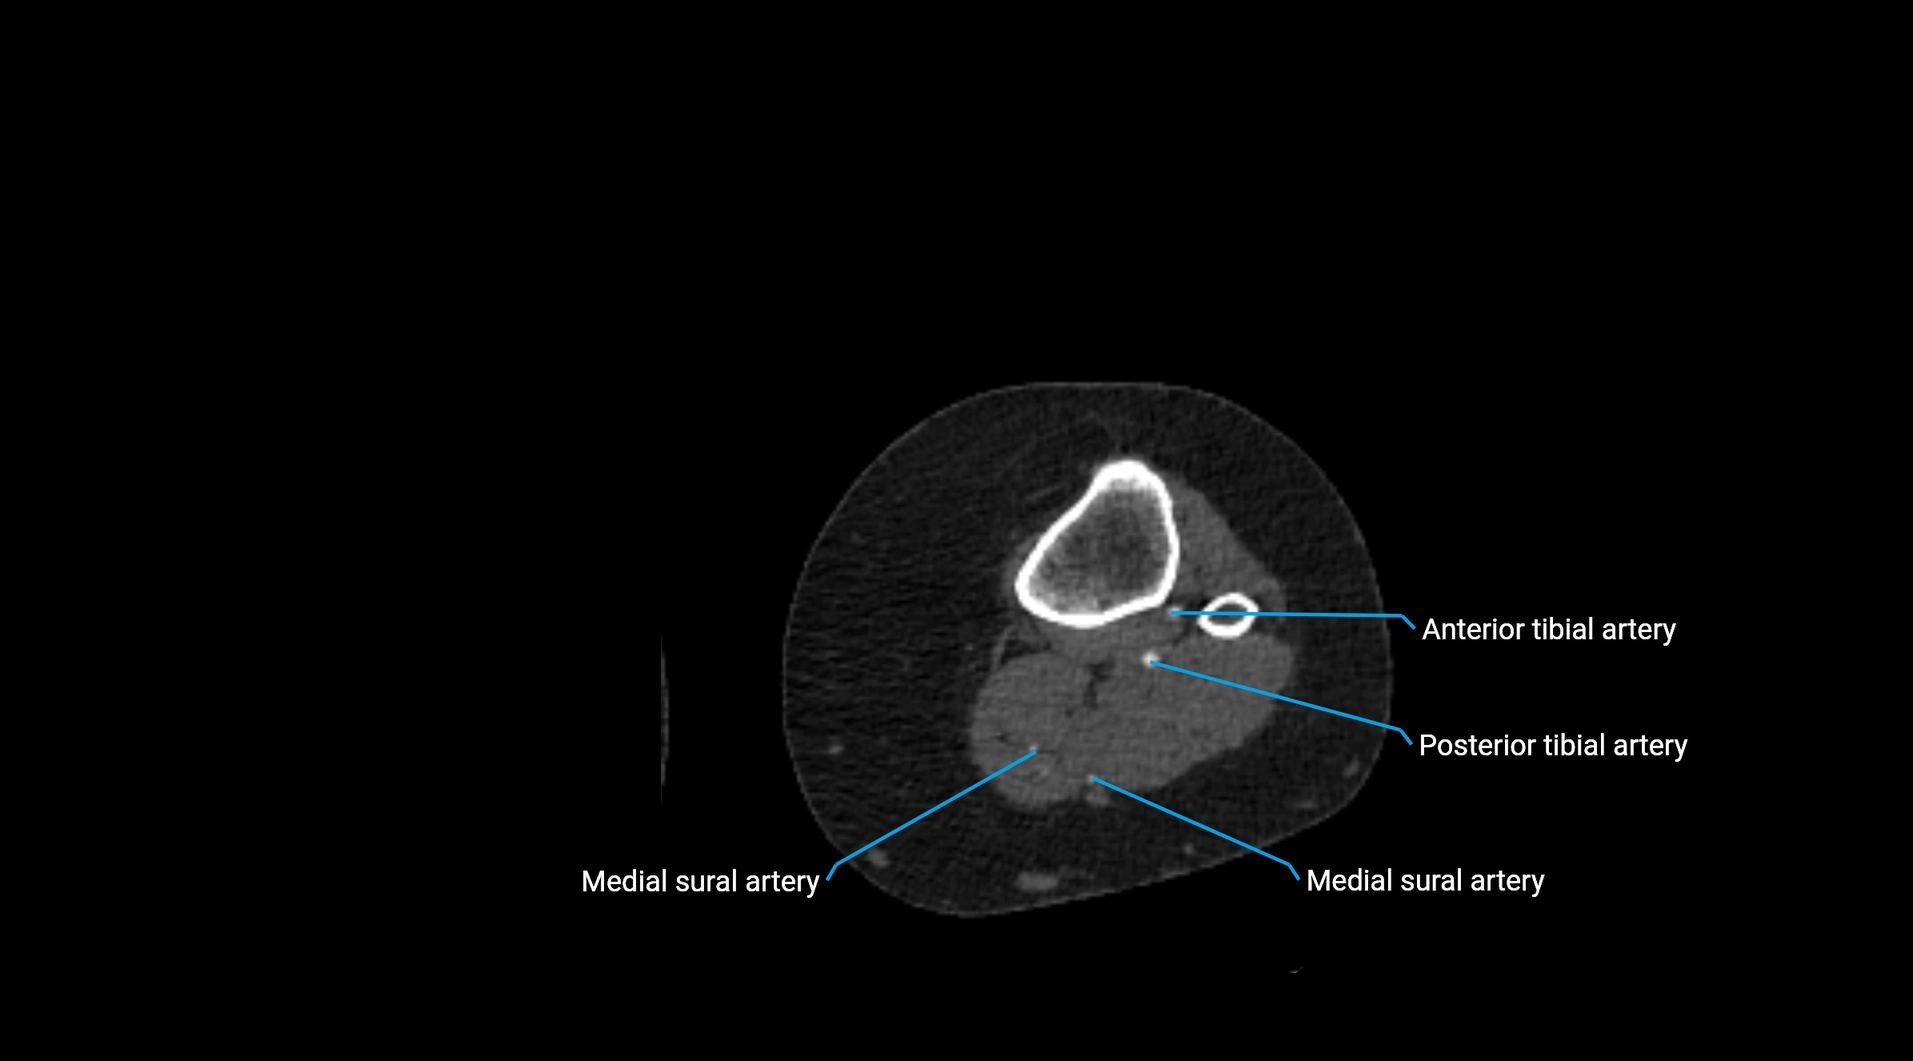

CT Appearance

Non-contrast CT:

• Appears as a tubular soft tissue structure anterior to vertebral bodies

• Calcified atherosclerotic plaques appear as hyperdense foci along the wall

• Useful for screening abdominal aortic aneurysm (AAA) size and mural calcification

Contrast-enhanced CT (CTA):

• Gold standard for abdominal aortic imaging

• Provides excellent detail of lumen, wall, aneurysm, thrombus, and branch vessels

• Multiplanar and 3D reconstructions help in aneurysm measurement, stent graft planning, and dissection evaluation

• Detects acute rupture, traumatic injury, or occlusion with high sensitivity